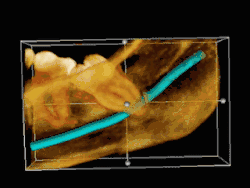

3D CT of an impacted wisdom tooth near the inferior alveolar nerve

Risk factors of inferior alveolar nerve damage

Temporary and permanent inferior alveolar nerve (IAN) damage is a known complication of the surgical removal of impacted lower third molars, happening in 1 in 85 patients and 1 in 300 extractions, respectively. Studies have shown that certain risk factors may increase the likelihood of IAN damage. Proximity of the impacted third molar root to the mandibular canal, which can be seen in radiographs, has been shown to be a high-risk factor for IAN damage. Alongside this, the depth of impaction of the tooth, surgical technique and surgeons experience are all contributing risk factors for IAN damage during this procedure. Careful case-by-case consideration is crucial to avoid this risk.[44]